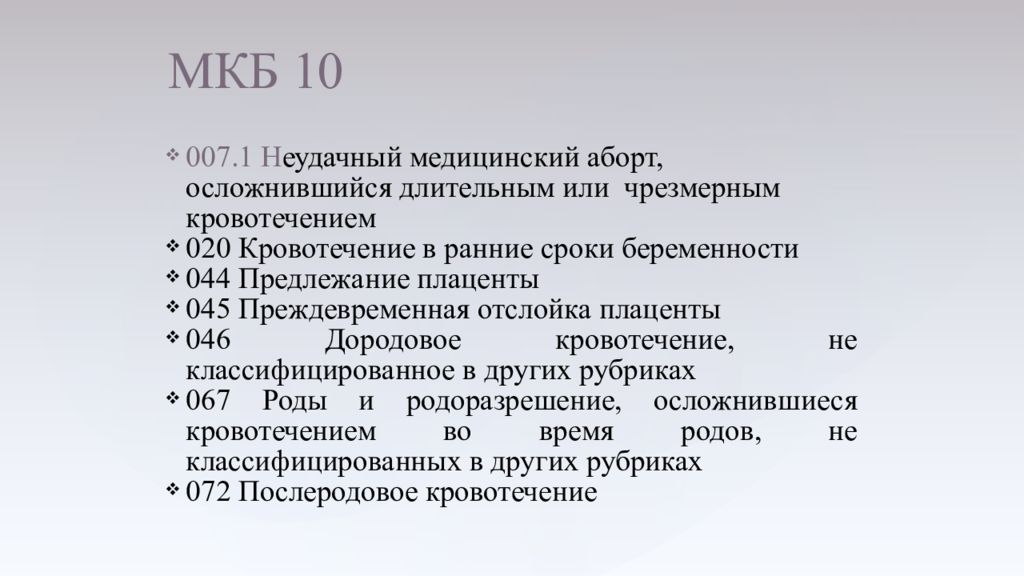

Острая внебольничная пневмония по МКБ-10: признаки и примеры